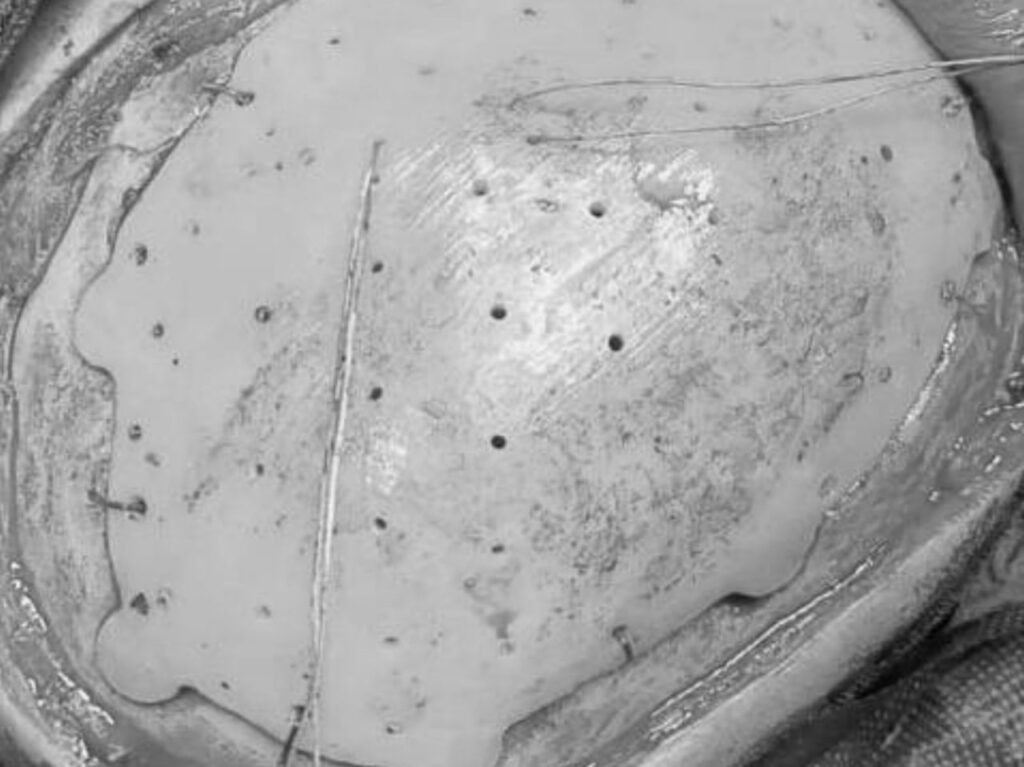

Хирурги Оренбургского центра хирургии и травматологии успешно провели операцию по восстановлению части черепа 19-летнему пациенту, пострадавшему в аварии.

После ДТП молодому человеку сделали экстренную трепанацию, в результате чего образовался сложный дефект свода черепа, доставлявший серьёзный косметический дискомфорт. Для операции был изготовлен индивидуальный имплант по 3D-снимкам компьютерной томографии.

Вмешательство прошло без осложнений, пациент выписан домой.

Фото: Оренбургский клинический центр хирургии и травматологии